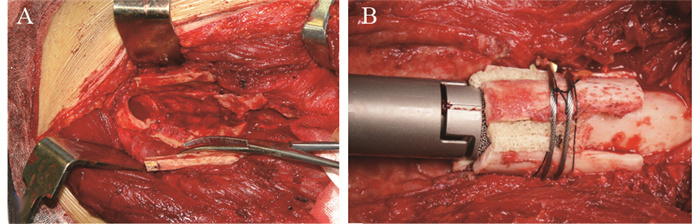

翻修手术包括两个步骤:第一步取出松动的假体,第二步置入新的假体。假体的各部分组件均需取出,包括没有出现松动的部分。采用骨水泥取出器械,尽量取出第一次假体置换时的骨水泥。器械包括各种尺寸的角刀、普通骨刀、超声骨刀、高速磨钻以及一次性冲洗枪。骨水泥取出后,采用扩髓器扩髓,有效长度残余皮质骨的厚度≥1 mm,以支撑假体柄。GMRS假体在假体柄体连接部分提供了一个多孔涂层结构,在这个区域,需要修理自体皮质骨做骨桥处理,见图 1A。具备多孔涂层结构的假体柄长度为4 cm,相应的皮质骨骨桥也设计为大约4 cm,需尽量保留该部分皮质骨的肌肉附丽和骨膜,以保证血液供应。在自体皮质带之间植入同种异体骨,并采用钢丝进行固定,见图 1B。假体柄均采用骨水泥进行固定,其余操作同常规人工关节置换。

![]() 图 1 术中自体皮质骨骨桥的处理Figure 1 Management of autogenous cortical bone bridge in operationA: the repair of the cortical bone of the distal femur, to form a bridge structure, with care to preserve the muscle attachments and periosteum surrounding the bridge; B: allogeneic bone was implanted between the gaps of the autogenous bone bridge and then fixed with steel wire.

图 1 术中自体皮质骨骨桥的处理Figure 1 Management of autogenous cortical bone bridge in operationA: the repair of the cortical bone of the distal femur, to form a bridge structure, with care to preserve the muscle attachments and periosteum surrounding the bridge; B: allogeneic bone was implanted between the gaps of the autogenous bone bridge and then fixed with steel wire.1.4 康复与随访